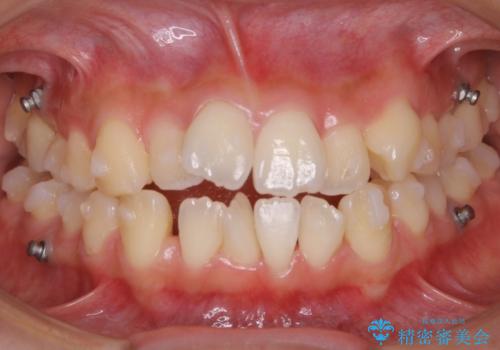

矯正装置の希望がインビザラインだったため、マイクロインプラントを併用し、奥歯から順に遠心移動をかけていくことにより非抜歯でも主訴のガタつきを治すことができました。

マウスピースとマイクロインプラントを組み合わせることで、抜歯をしなくても歯並びを治すためのスペースを作ることができます。奥歯から順に移動させていくので前歯に変化が出るまでには時間がかかりますが、その分健康な歯を抜歯することなく理想的な歯並びを手に入れることができます。